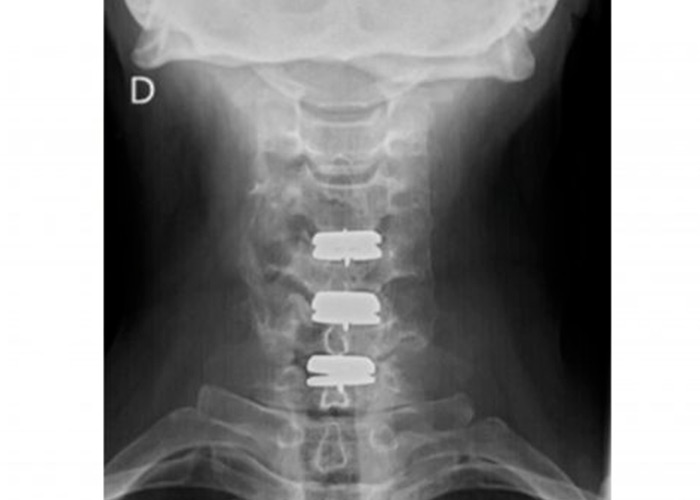

Tras haber probado todo tipo de tratamientos medico-rehabilitadores, el equipo de ICAC decide una intervención mediante técnica mínimamente invasiva y reconstrucción de los tres discos cervicales con prótesis móvil. La operación es un éxito y los resultados son notables inmediatamente.

protesis-cervical-movil-instituto-cac

Postoperatorio

En menos de 5 horas el paciente se recupera de la operación. Asimismo, la movilización del cuello comienza desde el primer momento y no se precisa collarín ni otros inmovilizadores.